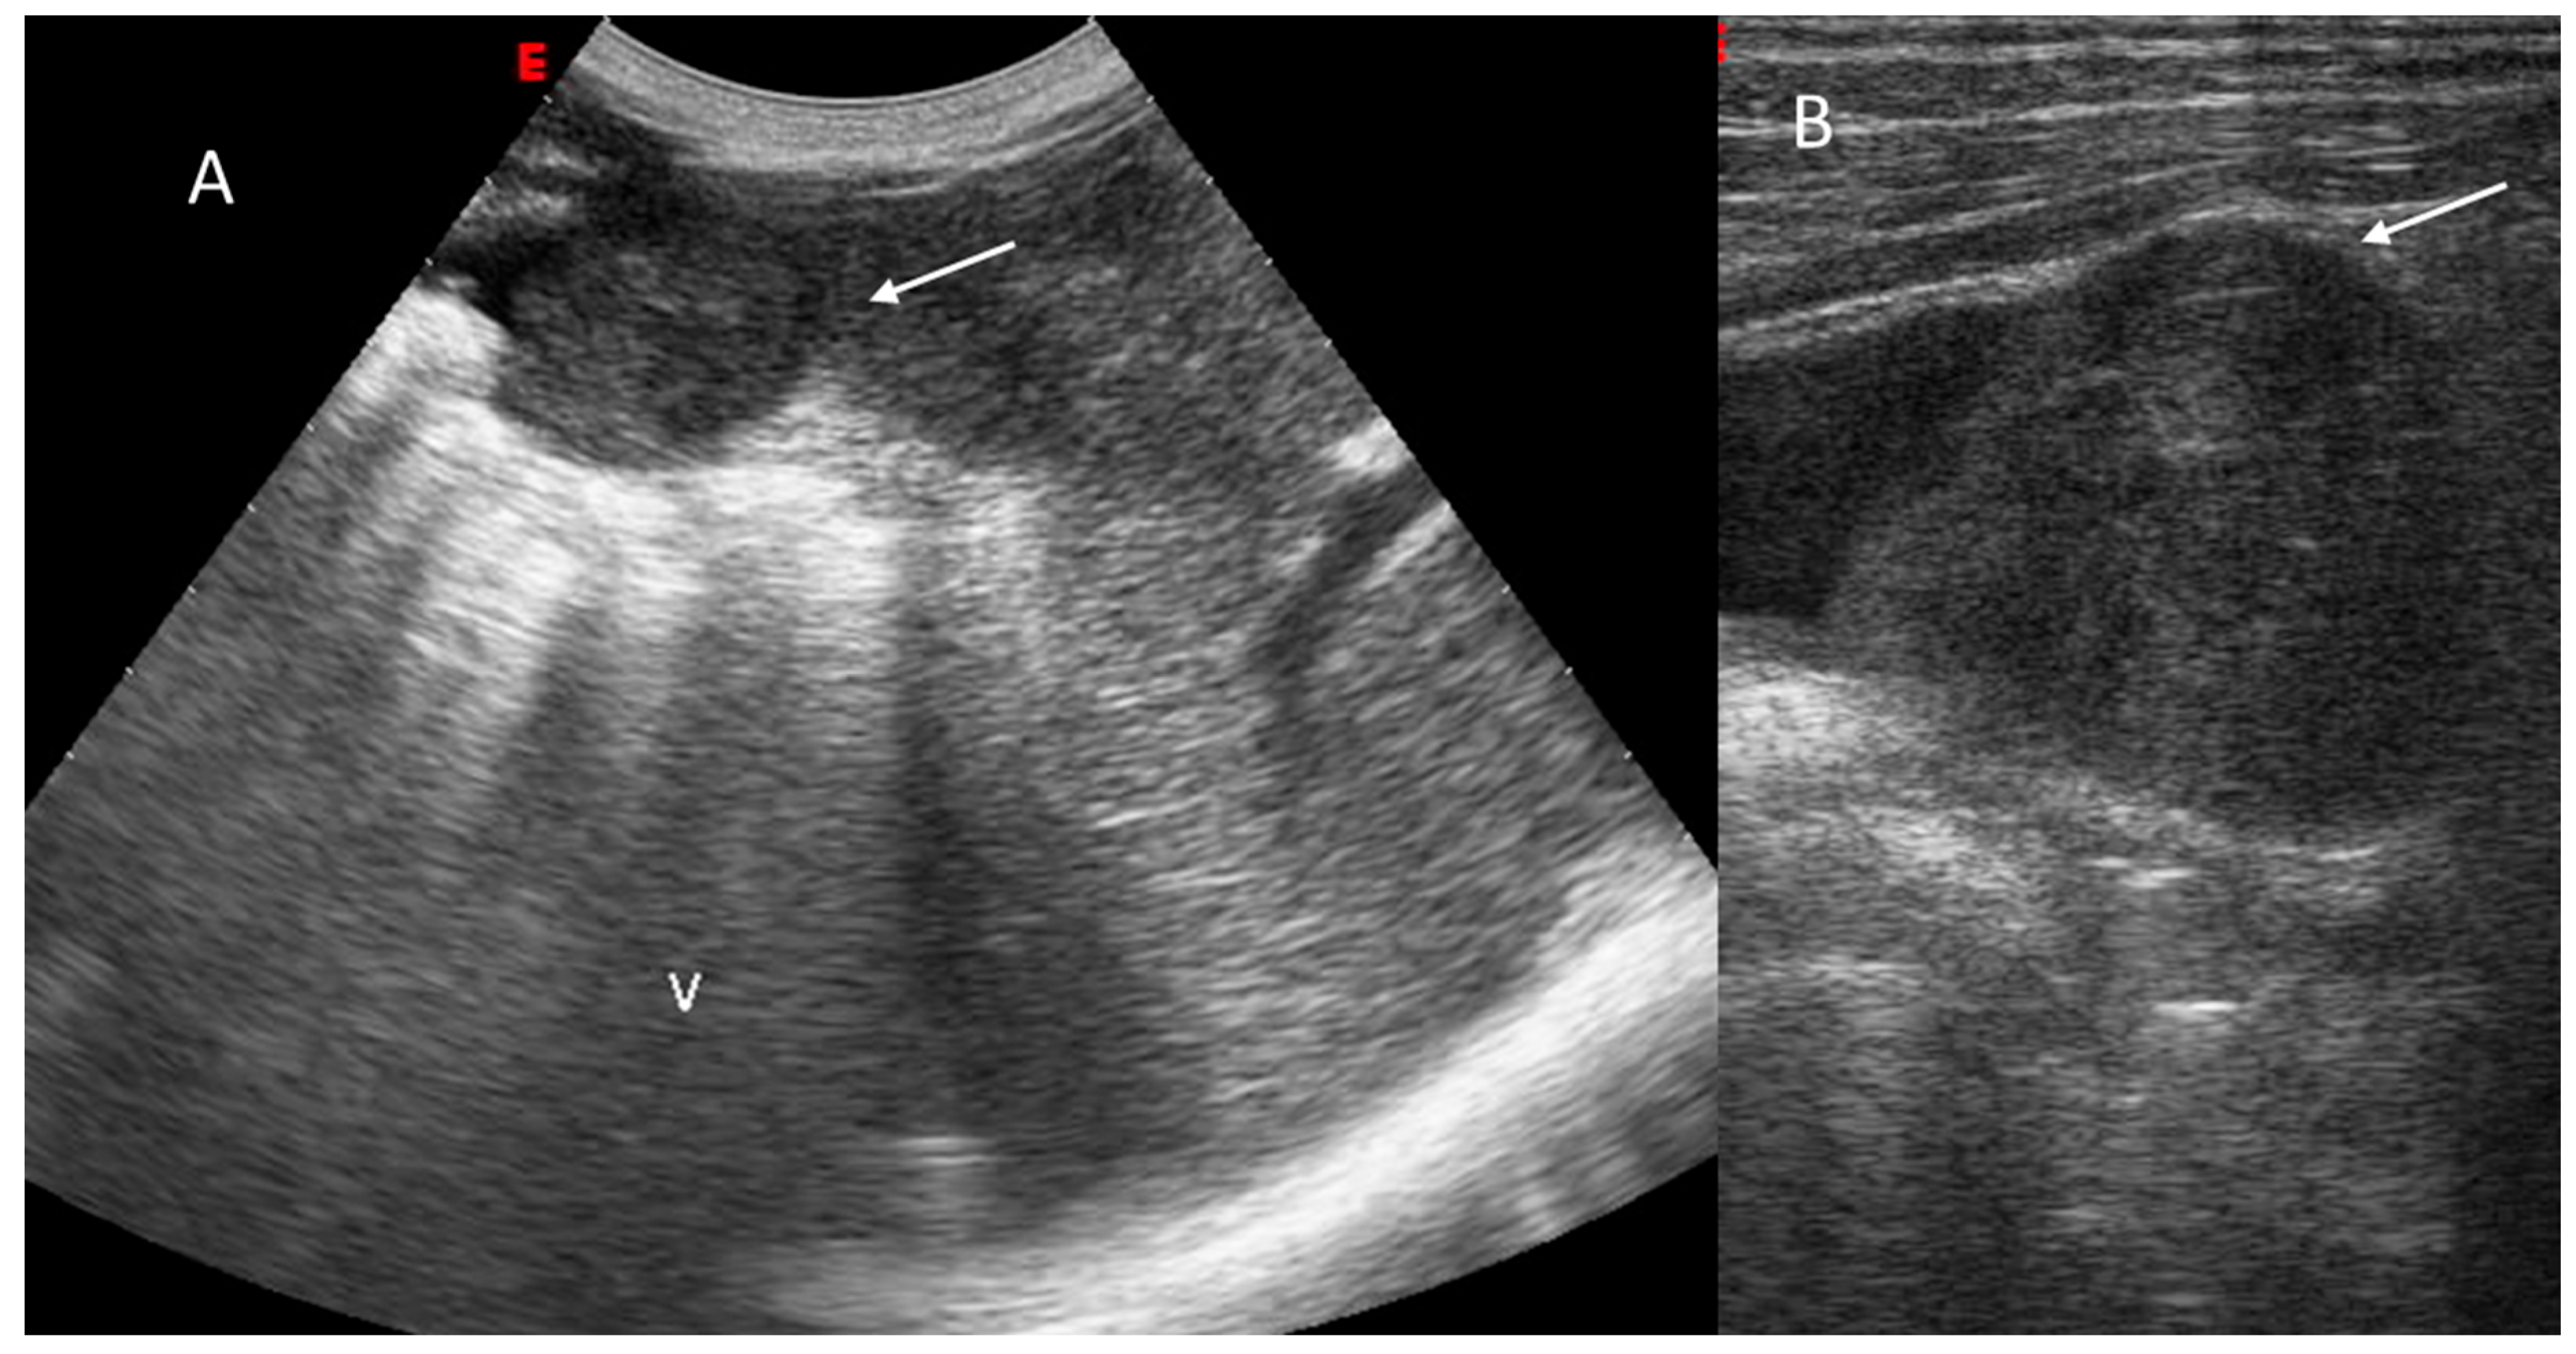

2.1. US-LI-RADS

2.1.2. Ultrasound Category and Visualization Score